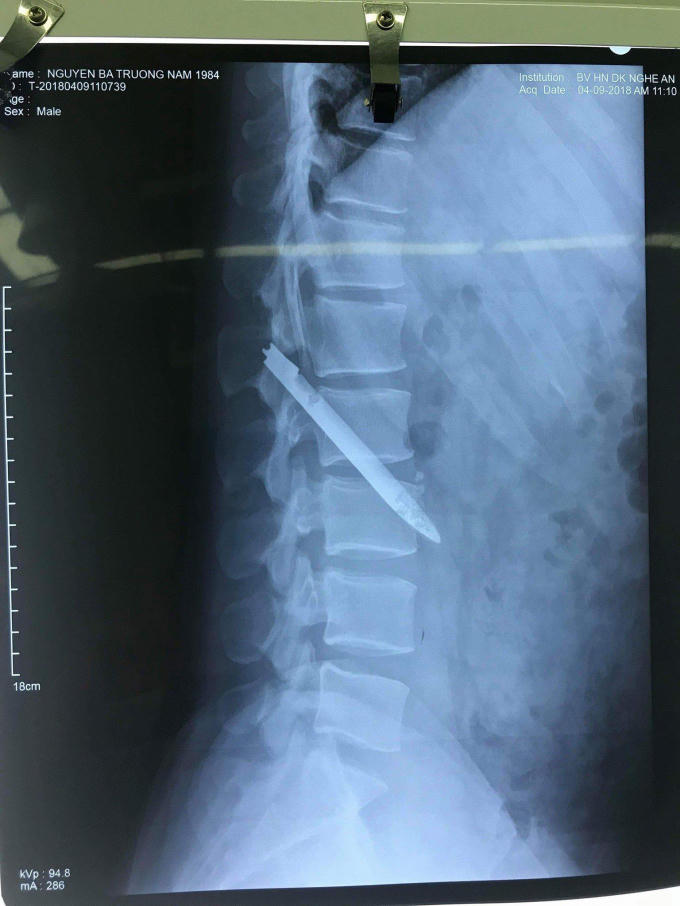

Qua thăm khám và hình ảnh chụp phim Xquang, các bác sỹ và bệnh nhân vô cùng ngạc nhiên khi phát hiện hình ảnh dị vật kim khí dài, mỏng nằm chéo vùng cột sống thắt lưng.

Xác định lưỡi dao trong cơ thể anh Nam tồn tại trong cơ thể đã lâu có thể gây biến chứng nguy hiểm, bác sỹ khoa Phẫu thuật Thần kinh cột sống chỉ định bệnh nhân mổ lấy dị vật ngay.

“Lưỡi dao nằm vị trí nguy hiểm, sát động mạch chủ bụng; chỉ cần bệnh nhân vận động mạnh có thể khiến nó di chuyển, gây tổn thương mạch máu, ảnh hưởng đến tính mạng nhanh chóng.